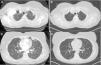

TC torácica. A) La TC inicial muestra un nódulo en el lóbulo superior izquierdo con cavitación; B) La TC con mayor resolución del nódulo en el lóbulo superior izquierdo tras 9 meses de seguimiento; C) La TC inicial muestra el nódulo periférico en la língula; D) La TC con mayor resolución del nódulo periférico en la língula tras 9 meses de seguimiento.

El factor de necrosis tumoral (TNF) es una citocina proinflamatoria sobreexpresada en los pacientes con AR. El American College of Rheumatology cuenta con recomendaciones oficiales sobre el uso de agentes biológicos anti-TNF en pacientes con AR con factores de mal pronóstico. Presentamos el caso de una mujer de 50 años que desarrolló consolidaciones nodulares multifocales, con y sin cavitación (figs. 1A y C), un mes tras iniciar tratamiento con etanercept. Se suspendieron los medicamentos inmunosupresores y el lavado broncoalveolar del lóbulo superior izquierdo y la língula fue negativo para etiología infecciosa. Al no haber confirmación de una infección, se reinició el tratamiento para la AR, exceptuando el etanercept. Una serie de estudios de tomografía computarizada (TC) mostraron la regresión de los nódulos en el intervalo. Se observaron cambios radiográficos en la TC de la visita de seguimiento a los 2 meses y ya no se han visto cambios a los 9 meses (figs. 1B y C).